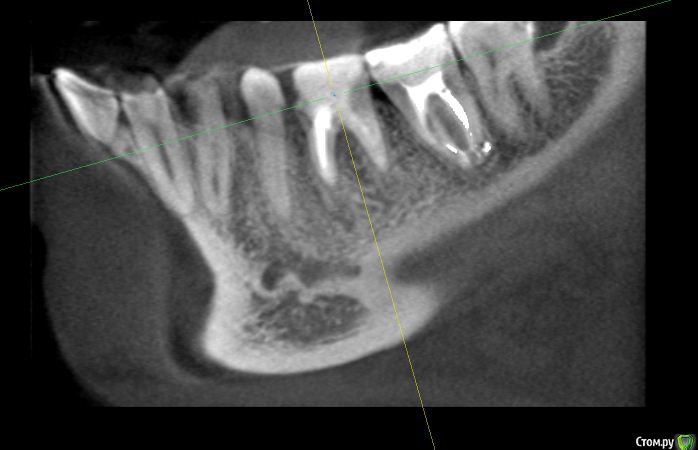

alex_ts Опубликовано 7 ноября, 2016 Поделиться Опубликовано 7 ноября, 2016 (изменено) Здравствуйте. Периодически беспокоит нижняя 6ка, 3 года назад она была на 3/4 разрушена и там стояла "металлическая" черная пломба, от которой зуб приобрел синий оттенок. На мой вопрос что его наверное надо удалять, стоматолог на меня тогда удивленно посмотрела и сказала что корни хорошие и ничего удалять не надо. Тогда же она поставила очень большую пломбу, сказав что это не на долго и так или иначе придется одевать коронку. Сейчас зуб время от времени побаливает и иногда кровит. Сходил в клинику, сделали кт зуба. Врач сказала что варианта 2, либо долго и сложно лечить этот зуб и протезировать, но без гарантии, так как там затемнение в области фуркации, либо удалять и ставить имплант. Что вы порекомендуете в данной ситуации? Спасать зуб или лучше будет избавиться от него? Мч, 24 года Изменено 7 ноября, 2016 пользователем alex_ts Ссылка на комментарий

anvladd Опубликовано 7 ноября, 2016 Поделиться Опубликовано 7 ноября, 2016 Лучше удалить,разрушен между корнями. 2 Ссылка на комментарий

DmitrySH Опубликовано 7 ноября, 2016 Поделиться Опубликовано 7 ноября, 2016 Плохой прогноз для лечения, удалять 2 Ссылка на комментарий

anvladd Опубликовано 8 ноября, 2016 Поделиться Опубликовано 8 ноября, 2016 Кариес под пломбой Ссылка на комментарий